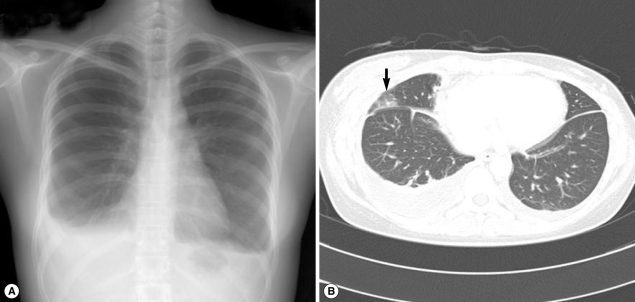

Fig. 1

Simple chest x-ray and computed tomography (CT) findings in case 1. (A) Pleural effusion (in the right lung) with evident fluid shifting is recognized in a lateral decubitus view. (B) Ground-glass opacity in the subpleural portion of the right lung and right hydropneumothorax (arrow).

A 51-year-old woman visited our hospital to seek treatment for general myalgia and lower extremity weakness that had persisted for 1 month. She had previously undergone magnetic resonance imaging (MRI) examinations of her cervical and lumbar spines to determine the cause of her lower extremity weakness; however, the results provided no clear explanation. Her chief complaints had not been resolved by traditional rehabilitation therapy. She had eaten Kejang together with her family a few weeks before. Her past medical history and social history was uneventful. An auscultation examination revealed a normal cardiac sound, but decreased breathing in the right lower lung zone. Otherwise, a physical examination yielded no specific findings. A complete blood cell count (CBC) revealed WBC levels of 23,900/mm3, hemoglobin levels of 11.9 g/dl, platelet levels of 393,000/mm3, absolute eosinophil count (AEC) of 14,400/mm3, and erythrocyte sedimentation rate (ESR) of 74 mm/hr. The woman's chemistry battery, and electrolyte and urine analyses revealed no abnormal findings. A simple chest x-ray revealed right pleural effusion (Fig. 1A). Chest computed tomography (CT) revealed hydropneumothorax in the right hemithorax (Fig. 1B) and infiltrative lesions suggestive of parasitic infections in the liver and peritoneum. As the clinical findings were indicative of a parasitic infection, antibody test by ELISA and stool examination were performed. We could not observe parasite eggs in the stool specimen; however, the ELISA results indicated the presence of Paragonimus antibodies, even though the total serum IgE levels were 18.2 IU/ml (within normal range). The patient was treated with praziquantel (25 mg/kg, 3 times a day, for 2 days). A week after the medication, the patient's eosinophil count decreased from 14,400/mm3 to 4,250/mm3, her left pleural effusion was improved, and her chief complaints were resolved.

Fig. 1 Simple chest x-ray and computed tomography (CT) findings in case 1. (A) Pleural effusion (in the right lung) with evident fluid shifting is recognized in a lateral decubitus view. (B) Ground-glass opacity in the subpleural portion of the right lung and right hydropneumothorax (arrow).